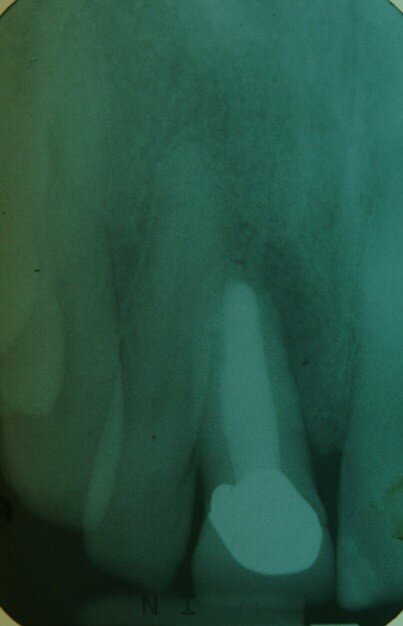

Patient RR was a healthy non-smoking 44 year old male who presented with a complaint of an unaesthetic upper right central incisor with extensive recession showing a large amount of darkened labial root surface. The situation was worsened by a high smile line and a porcelain crown contrasting dramatically with the root colour. He had had periodic swelling at the apical part of the recession over a long period. There was a history of trauma in his teens leading to root canal treatment and a crown, and subsequent apicectomy in his 20s. Clinical examination revealed an otherwise periodontally healthy, well looked-after mouth. (Fig. 1, 2, 3)

Diagnosis was of endodontic failure and possible root fracture leading to loss of labial bone and soft tissue.